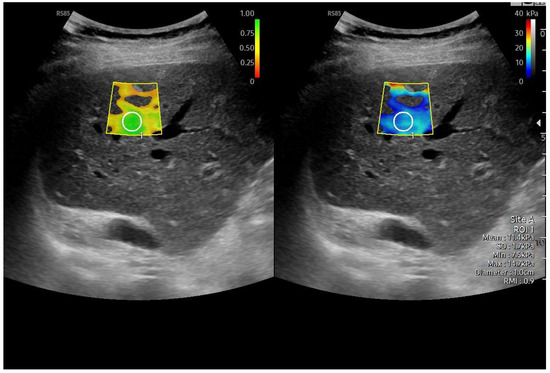

Abdominal ultrasound is a fundamental diagnostic tool in clinical practice, due to its availability, safety, and overall accuracy. This Special Issue will delve into the most recent technological and methodological innovations in abdominal ultrasound imaging, offering readers a comprehensive overview of advanced techniques, specific clinical indications, and solutions to emerging challenges. Among the various topics, it will cover the use of high-resolution probes, the integration of elastography for assessing liver fibrosis, and the application of contrast-enhanced ultrasound for identifying complex lesions. Strategies for training and professional development will also be examined to improve ultrasound performance and result interpretation.